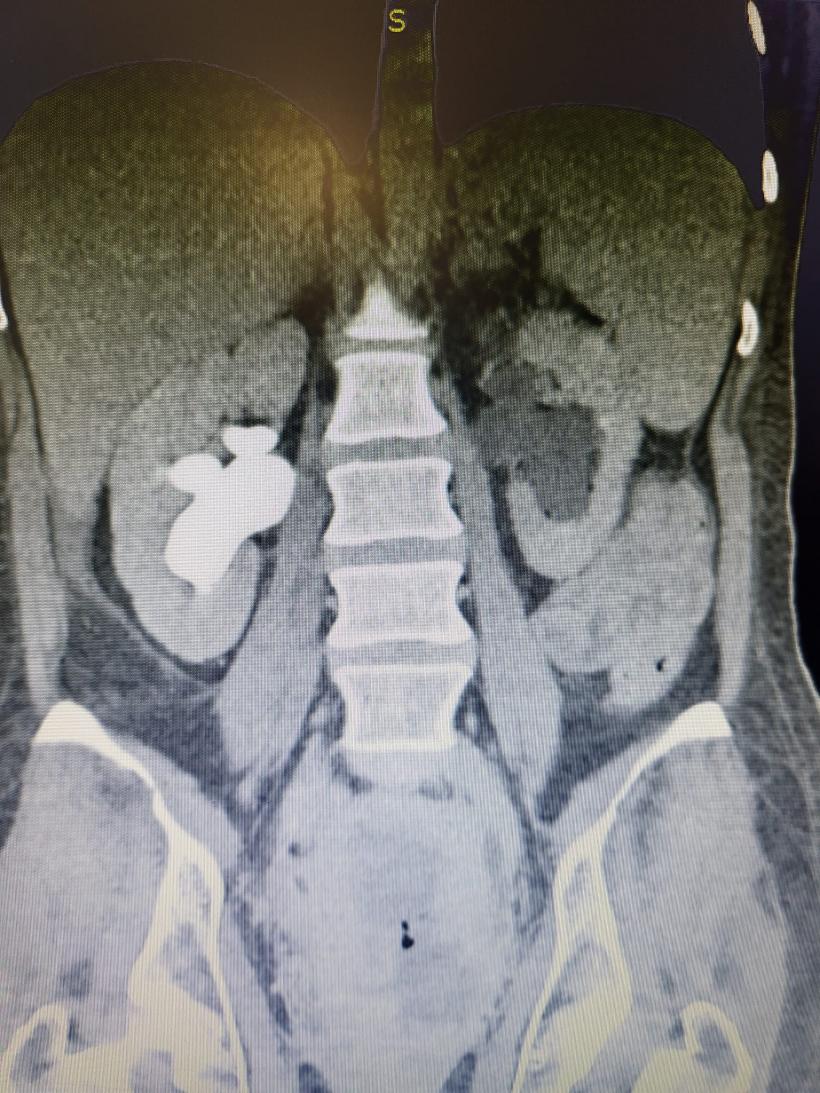

Tânără de 37 de ani trimisă să moară, salvată de medicii din Brașov: De cele mai multe ori imposibilul e posibil! | Galerie Foto | Imagine 2

Facebook Bogdan Moldovan